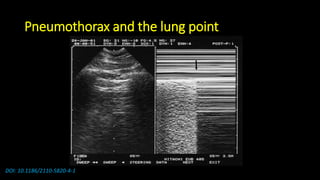

Pneumothorax and the stratosphere sign

DOI: 10.1186/2110-5820-4-1

Pneumothorax and the lung point